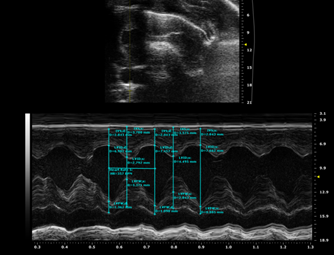

模型評價

3573634484425250063-14

圖注:TAC模型心電圖

圖注:TAC模型4周后心電圖